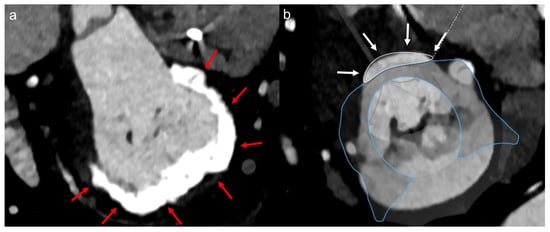

2.3. Computed Tomographic (CT) Assessment